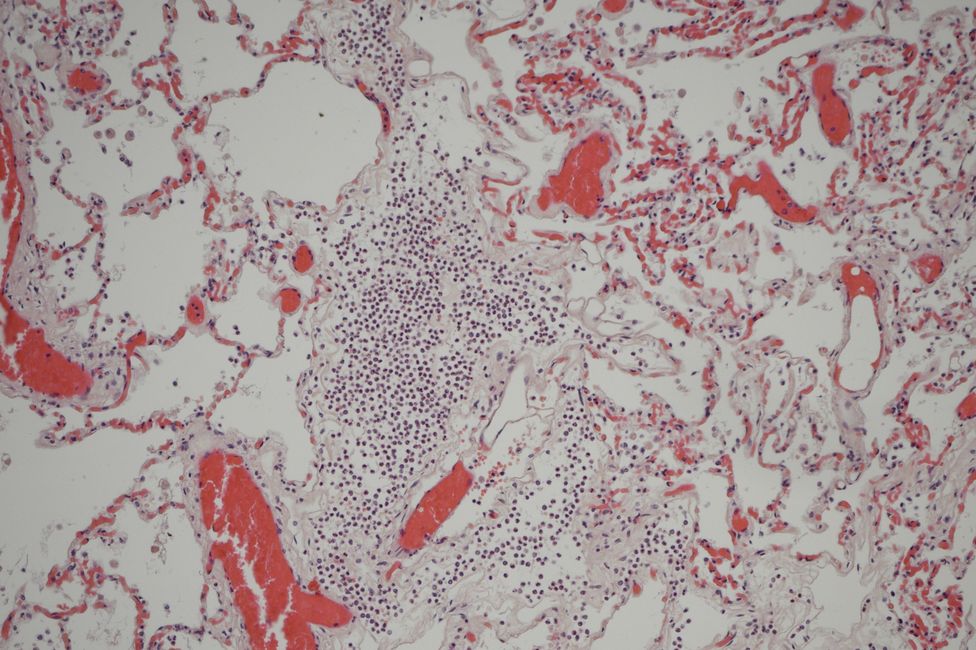

Die forensische Histologie nimmt eine wesentliche Rolle im Rahmen von gerichtlichen Leichenöffnungen ein, da mit spezifischen histochemischen und immunhistochemischen Färbemethoden Aussagen zur Todesursache, z.B. sauerstoffmangelbedingte frühe Organschädigungen, erkannt, aber auch Altersbestimmungen von Verletzungen und Vitalitätsprüfungen durchgeführt werden können.